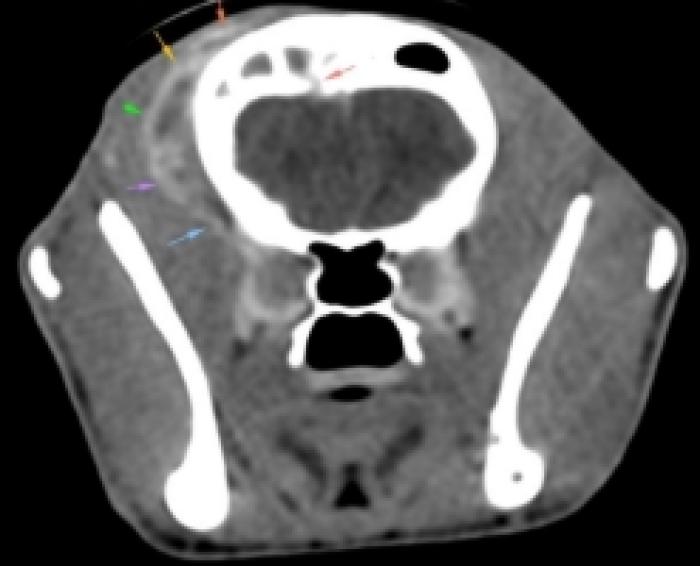

Revisión clínica y control analítico (día 35): a pesar del tratamiento instaurado, el paciente acude de urgencia debido a que el cuadro progresa con signos neurológicos centrales: marcha en círculos, pressing, anisocoria (pupila izquierda miótica y derecha midriática), respuesta a la amenaza y reflejos pupilares directos e indirectos negativos bilateralmente. El paciente no presenta hipertensión ni alteraciones en el fondo de ojo. Se repite hemograma, con empeoramiento del leucograma y fructosamina, con valor nuevamente más bajo, modificándose la pauta de insulina a 2 UI/12 h (Tabla 2) y se añaden ecografía abdominal (sin alteraciones relevantes) y bioquímica completa con parámetros hepáticos (transaminasas, bilirrubina y ácidos biliares pre-prandiales), lipasa específica felina y tiroxina total en rango fisiológico. Ante la sospecha de infección intracraneal, se añade a la pauta de antibioterapia trimetoprima-sulfametoxazol a dosis de 15 mg/kg/12 h y se realiza tomografía computarizada (TC) de cráneo.

TC: efecto masa compatible con absceso, ocupando senos frontales, con osteomielitis del hueso frontal derecho, miositis y absceso en musculatura temporal derecha en contacto con hueso frontal, afectación intracraneal en área epidural del lóbulo temporal derecho con desviación de línea media de hemisferios (sin afectación de parénquima). Se observa además moderada pérdida de cornetes nasales en cavidad nasal derecha, sin secreciones asociadas y linfadenopatía regional derecha de tipo reactivo (Figura 6A-F). Se drena el contenido del absceso más superficial y se envía al laboratorio externo para su estudio microbiológico (cultivo y antibiograma).